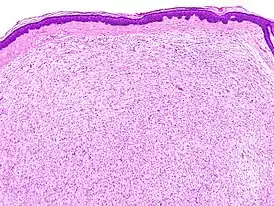

![]() Гистологическое изображение кожной нейрофибромы | |

Общим для структуры нейрофибром является беспорядочное расположение нервных волокон внутри периневрия, где они разделены клетками соединительной ткани. Инкапсулированные нейрофибромы возникают главным образом в крупных нервах. Нерв при этом приобретает на некотором протяжении веретенообразную форму за счёт очагового беспорядочного разрастания нервных волокон, разделённых пучками коллагеновых волокон. В нейрофибромах кожи нервные волокна иногда бывает трудно обнаружить, так как они представлены очень скудно. В инкапсулированной нейрофиброме часто отмечают нарушения лимфообращения, проявляющиеся признаками выраженного отёка. По мере распространения отёка из периневрального пространства на внутреннюю часть нервного ствола усиливается его разволокнение, миелиновые волокна исчезают и заменяются фиброзными тяжами. Дальнейший рост такой нейрофибромы постепенно замедляется и может приостановиться[1].

Диффузная нейрофиброма возникает главным образом в результате поражения мелких нервов кожи. Довольно часто диффузная нейрофиброма состоит из вытянутых леммоцитов (шванновских клеток). В диффузной нейрофиброме иногда обнаруживают пигментные клетки и рецепторы (типа телец Мейснера и Фатера-Пачини). Нейрофибромы, возникающие в симпатическом стволе, могут включать ганглиозные клетки и по микроскопической картине иногда напоминают неинкапсулированную ганглионеврому[1].